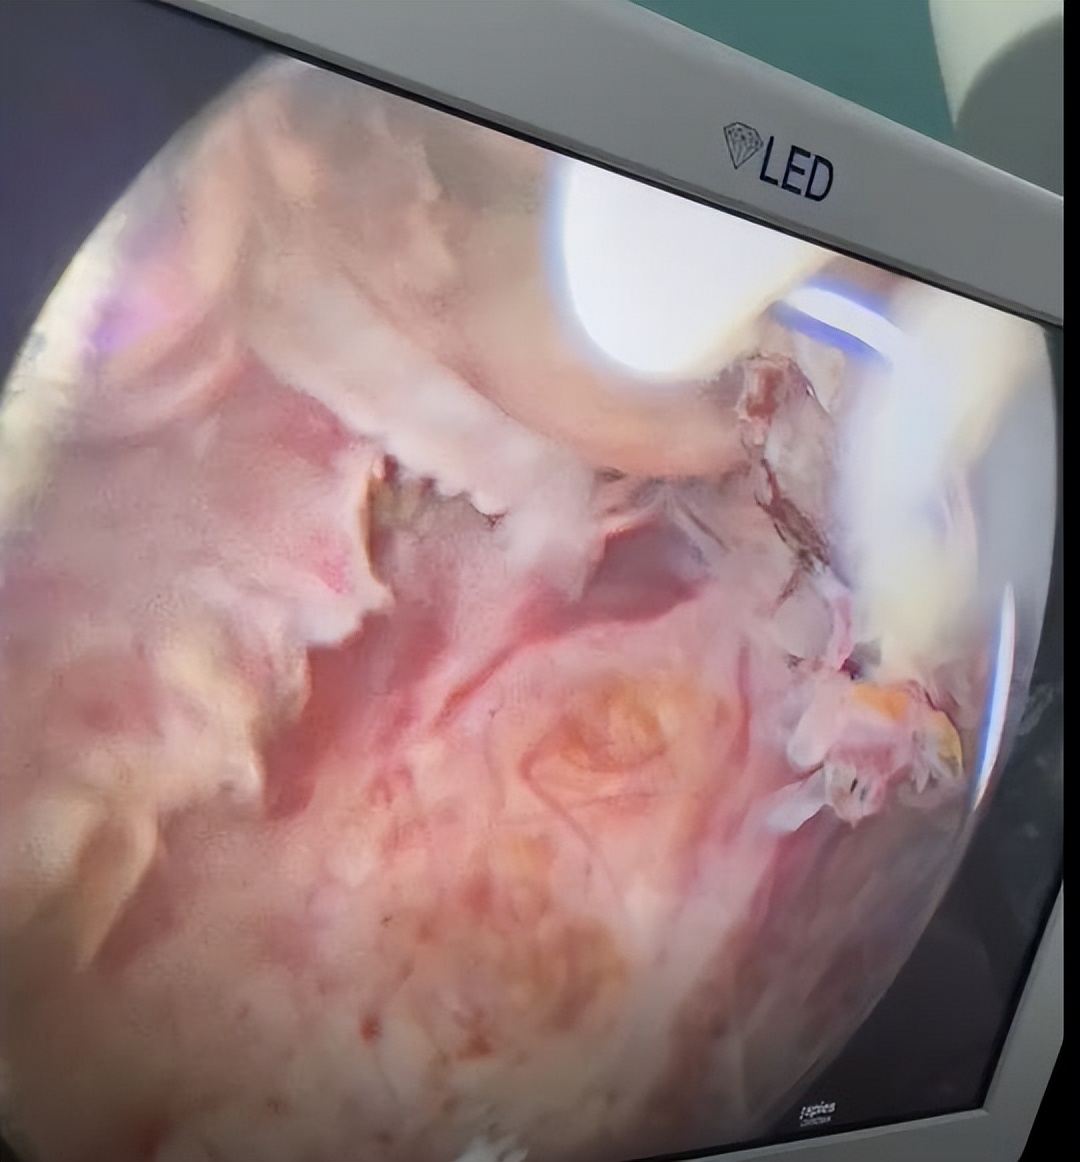

“不好!可能是囊性腺肌瘤破裂了!” 时值周日, 医院马上启动了紧急处理程序,赵秀敏为杨女士做了急诊宫腔镜手术。

宫腔镜下,可以看到杨女士宫颈部位已出现了一个巨大的破口,情况十分危急。

△杨女士宫腔镜提示巨大空洞样改变,丰富的血管和淡黄色的陈旧性出血灶